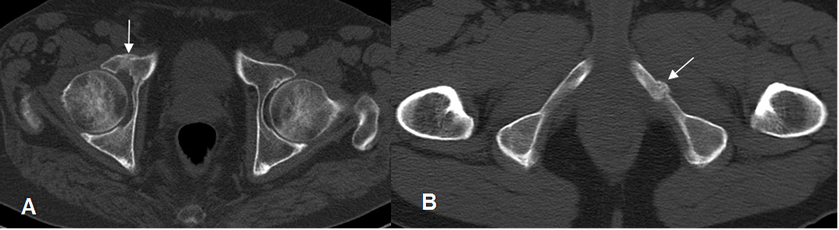

Fig 72. Fractura de stress.

A y B: TAC axial. Formación de callo óseo en el acetábulo derecho y ramo isquiopúbico izquierdo, por fracturas de stress.